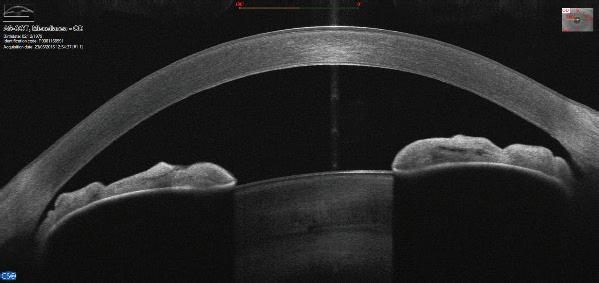

MS39 AS OCT

Συνδυασµός OCT προσθίου (εύρους 16 mm) και τοπογραφίας Placido.

Προσφέρει:

• Ανάλυση για όλο τον πρόσθιο θάλαµο

• Πρόσθια και οπίσθια τοπογραφία κερατοειδούς και τοµογραφία.

• Παχυµετρία Κερατοειδούς –Επιθηλίου & Stroma

• Γονιοσκόπηση

• Έλεγχος Γλαυκώµατος

• Έλεγχος Κερατόκωνου

• Προεγχειρητικός Έλεγχος Καταρράκτη

• Προηγµένη IOL Βιοµετρία

• Μελέτη Dry Eye µε λειτουργίες , όπως NIBUT, Tear Film Analysis, Meibomian Glands

• Pupilography

35 www.minopta.gr Club.Minopta.gr 29